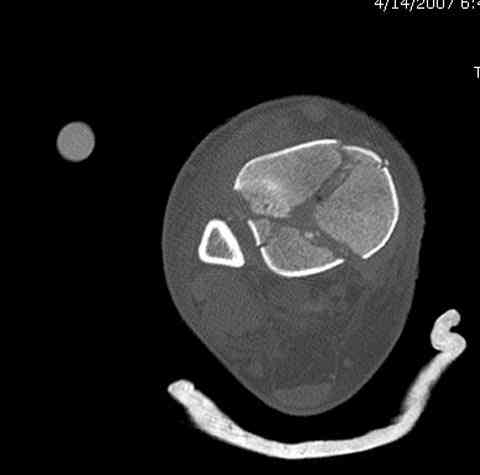

Дополнительные ренгенограммы после дистракции и

обязательная комьютерная томография дают возможности разузнать топографию расположения фрагментов, что немаловажно для планирования хирургического доступа.

По апексу фрагмента ориентируется при планировании

фиксации, также предоперационно определяется

направление фиксирующего материала: шурупа или спицы с упорной площадкой.

Переломы пилона сопровождаются ударом со сминанием в метафизарной части большеберцовой, то есть со значительной потерей костного объема.

При репозиции суставных поверхностей образуются полости в метафизарных отделах, без заполнения их

структуральными элементами невозможно предохраниться от посттравматической деформации. Латеральная колонна удерживается малоберцовой поэтому голень деформируется в варус.

Здесь выставлена пара случаев перелома пилона, оба

случая леченные этапным наружным фиксатором.

Второй случай фиксирован аппаратом Илизарова.